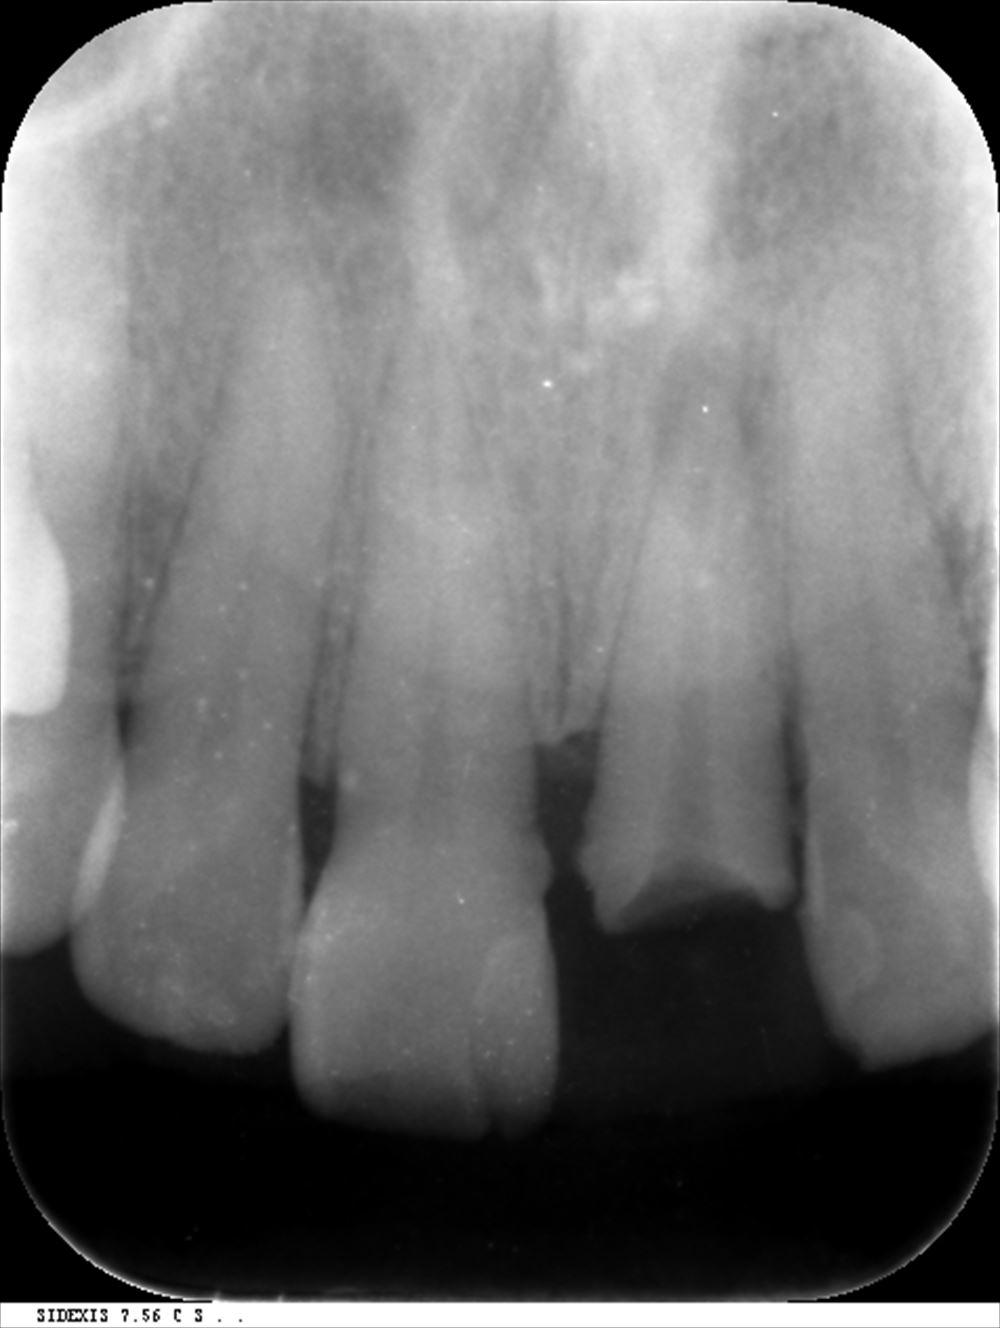

このケースは他院で説明がなく不安で当院に。歯科ドック後根管治療

根の先が見えるようにストレートラインアクセス

根管充填。3回で根管治療終了

術前

術後 症状も消えました!!